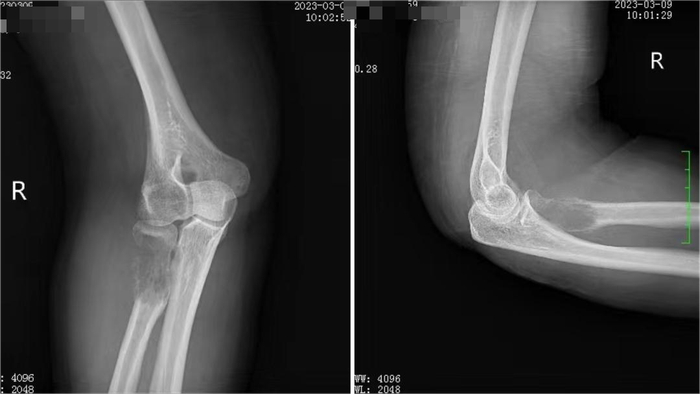

术前影像资料

右尺骨近端团块状异常信号影(—范围约21mm×34mm)